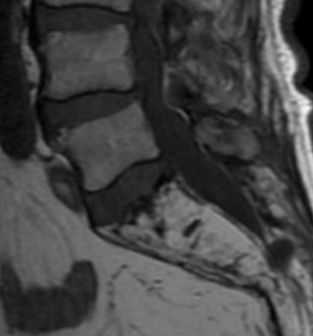

(Справа) На аксиальной КТ-дискограмме отмечается распространение контраста из центральной части, соответствующей пульпозному ядру, в срединный дефект фиброзного кольца, распространяющийся до эпидурального пространства. (Слева) Т1-ВИ: выраженные из -менения замыкательных пластинок II типа на уровне L4-L5 (жировая перестройка) со значительным снижением высоты диска. На соседнем уровне L3-L4 признаки I типа изменений в виде снижения интенсивности сигнала костного мозга и незначительно выраженный спондилолистез.

(Справа) На сагиттальном STIR МР-И на уровне L3-L4 отмечаются выраженные дегенеративные изменения замыкательных пластинок I типа. Также здесь видны незначительный антеролистез L3 и признаки дегенерации межпозвонковых дисков на различных уровнях.